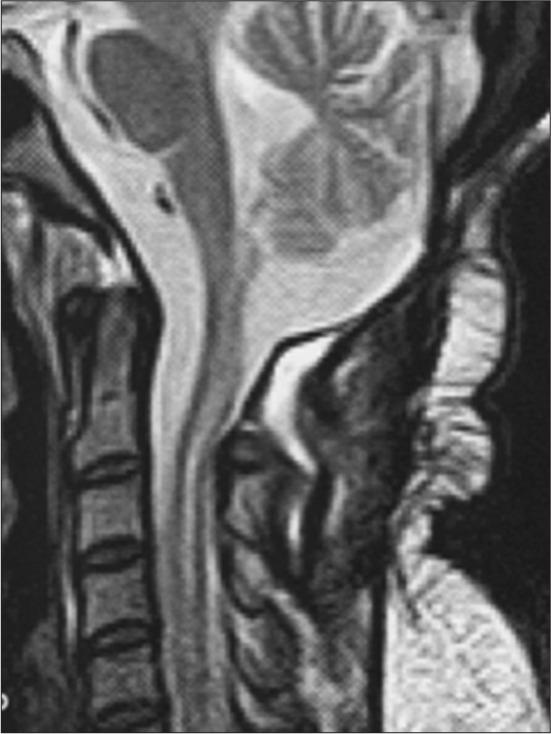

CASE DESCRIPTION

A 32-year-old female presented with persistent headaches with a cervical MRI showing an intradural and extradural mass extending from the obex to C2. Following surgical tumor resection, the patient's symptoms resolved.

一名32岁女性因持续性头痛就诊,颈椎MRI显示硬膜内和硬膜外肿块,从延髓下部延伸至C2。手术切除肿瘤后,患者症状缓解。